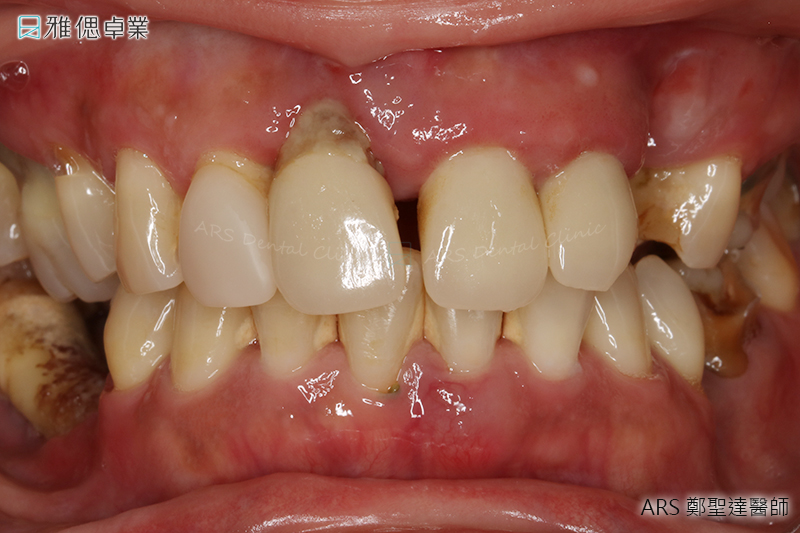

牙周病的症狀

牙齦流血

牙齦從粉紅色變為暗紅色,刷牙或平時出現牙齦出血症狀

牙齦紅腫

牙齦腫脹、有觸痛感或產生膿包,當牙齦受壓時有膿從牙齒和牙齦之間流出

牙縫變大

牙齦萎縮,使牙根暴露及牙縫變大

牙齒搖動

牙齒鬆動或咀嚼無力

因牙周病較少出現疼痛症狀,民眾多容易輕忽,誤以為只是火氣大而導致延誤就醫。若您發現自己有以上症狀,建議盡快預約牙醫師進行檢查。